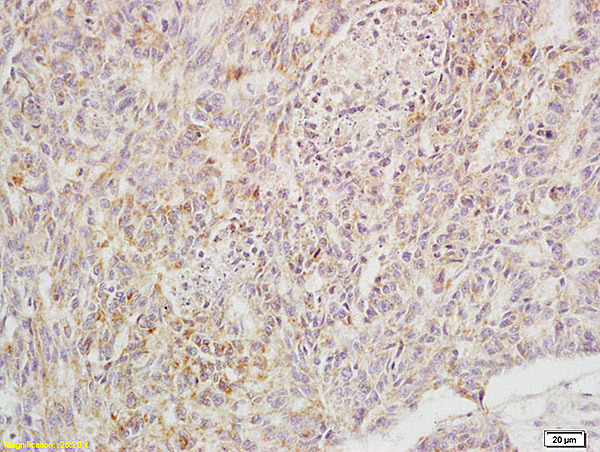

- Main image

- Experimental details

- Formalin-fixed and paraffin embedded rat brain labeled with Anti-ULBP3/N2DL3 Polyclonal Antibody, Unconjugated (bs-2730R) at 1:200 followed by conjugation to the secondary antibody and DAB staining

- Sample type

- Rat

- Other comments

- Brain